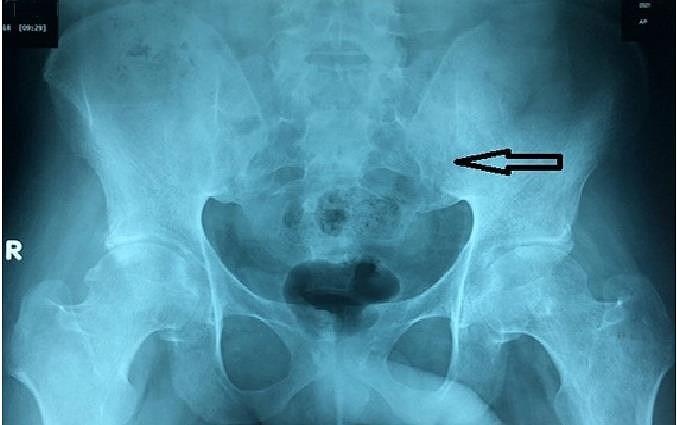

| Kết quả chụp X quang cho thấy khung chậu bệnh nhân bị tổn thương khi nhập viện. Ảnh: Pháp Luật TP.HCM. |

Chẩn đoán bệnh nhân bị viêm cột sống dính khớp, BS quyết định điều trị bằng thuốc đặc hiệu. Sau 6 tuần điều trị, bệnh nhân có thể đi lại dễ dàng.